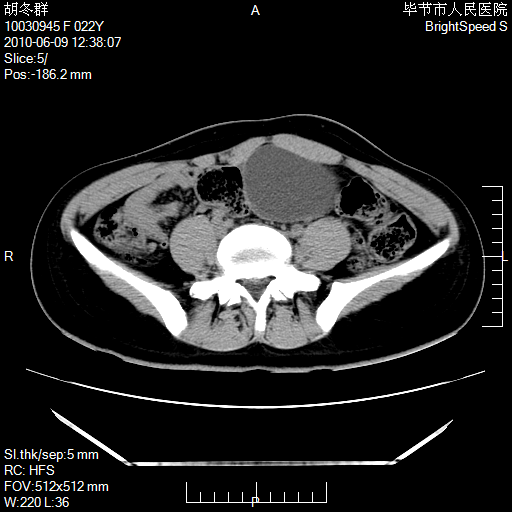

患者23岁,发现腹部包块3月。

左侧卵巢囊腺瘤或囊腺癌

盆腔内囊性占位性病变;考虑左侧卵巢囊腺瘤。

有分隔、壁薄,支持考虑左侧卵巢囊腺瘤。

左侧卵巢浆液性囊腺瘤。

支持考虑左侧卵巢囊腺瘤;宫腔积液。

有分隔、壁薄,支持考虑左侧卵巢囊腺瘤。排尿后,膀胱缩小,由于重力作用,肿块下移就到了膀胱位置,很好理解。